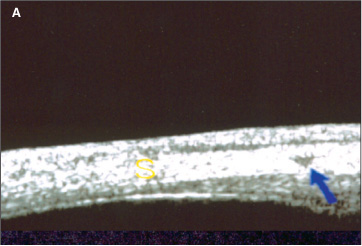

Paciente 4: 11 anos, sexo feminino, leucodérmica. História de convulsões na infância, sendo usuária de primidona (250 mg ao dia). Ao exame, apresentava hemangioma facial bilateral acometendo pálpebras e pescoço; acuidade visual igual a 0,35 no OD e 0,7 no OE, sob correção; Po igual a 36 mmHg no OD e 32 mmHg no OE; à biomicroscopia, mostrava formação plexiforme vascular vinhosa no limbo nasal e temporal em AO; à gonioscopia, seio camerular do tipo intermediário com a raiz da íris aparentemente implantada ao nível do esporão escleral; à fundoscopia, mostrava papila atrófica com escavação de 0,9 no OD e papila rósea com escavação de 0,4 a 0,5 no OE e angioma de coróide em AO. Foi submetida a trabeculectomia com mitomicina C (0,3 mg/ml durante três minutos), de urgência, em AO, usando-se no pré-operatório 250 ml de manitol IV. Os achados da UBM realizada sob timolol, antes da cirurgia, foram em AO: imagem triangular intra-escleral de média ecogenicidade no quadrante superior compatível com vaso intra-escleral dilatado (similar à fig. 3a); imagem arredondada de baixa a média ecogenicidade no interior do corpo ciliar nos quadrantes superior e temporal, compatível com vaso intraciliar dilatado ou angioma do corpo ciliar (similar à fig. 3b); efusão supraciliar (fig. 4, seta amarela) e descolamento da pars plana nos quadrantes superior e inferior no OD e no quadrante temporal no OE; imagem intra-escleral em fenda, de trajeto oblíquo, compatível com a possibilidade de vaso ou canal emissário (fig. 4, seta azul) no quadrante superior do OD. Quatorze meses após a cirurgia, a paciente apresentava Po igual a 6 mmHg sem medicação em AO. Repetiu-se a UBM em AO, encontrando-se achados similares aos do pré-operatório.

Paradoxalmente, o achado mais importante da UBM foi a presença de efusão supraciliar apenas nos olhos com glaucoma (seis dos nove olhos glaucomatosos, metade deles em uso de medicação tópica antiglaucomatosa). A paciente 3 tinha glaucoma mas não efusão supraciliar. É possível que a paciente 3, no qual a UBM mostrou imagens compatíveis com vaso intra-escleral dilatado e vaso ciliar dilatado ou angioma do corpo ciliar e cuja idade, na época da realização do exame, era de 5 anos, também apresentasse efusão supraciliar não diagnosticada pelas dificuldades inerentes à realização do exame (feito sob narcose e sem possibilidade de movimento dos olhos).